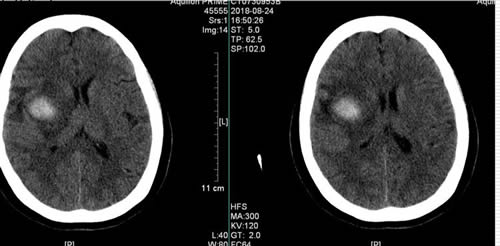

50岁的林女士因突发头疼,左侧肢体无力,无法行动,经MRI检查显示,其脑深部病变,合并出血,医生诊断为右侧基底节区巨大海绵状血管瘤破裂出血。据主管医生江常震副主任医师介绍,此类肿瘤位置越深,手术难度越大,林女士的血管瘤直径3.5cm,且脑部病变位置深,位于皮层功能区深部,难以准确暴露,且周围有重要的神经纤维束(皮质脊髓束)紧贴瘤壁穿行,使得手术难度加大,虽然显微镜下手术已有开展,但稍有不慎,便有造成永久性瘫痪或偏瘫的风险。

历时3小时,在康德智教授团队的努力下,血管瘤所在位置被准确定位并顺利切除。术后CT提示血管瘤完全切除,功能MRI复查深部神经纤维束均正常。目前患者左侧肢体肌力较术前明显改善,可下床行走,生活基本自理。